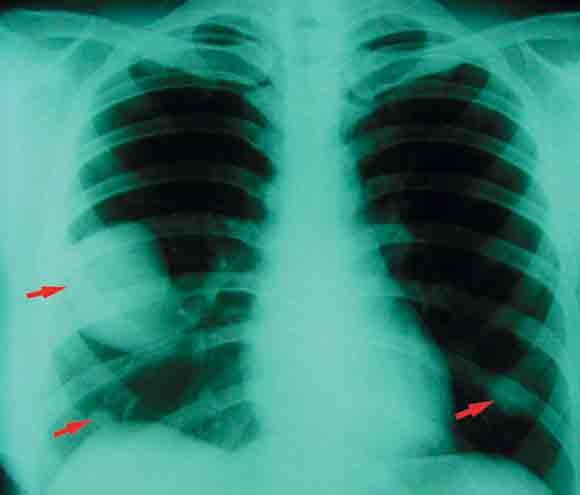

A 28-year-old woman presented with a 3-month history of wrist and ankle pain, lethargy and weight loss. She had clubbing of the fingers (Box 1) and toes. A bone scan (Box 2) and chest x-ray (Box 3) revealed periostosis in the wrists and pulmonary metastases, respectively. Two years earlier she had been diagnosed with a malignant phyllodes tumour of the left breast (Box 4), which was treated by mastectomy and axillary dissection.

Hypertrophic osteoarthropathy (HOA) secondary to pulmonary metastatic phyllodes tumour was diagnosed. HOA is a paraneoplastic syndrome characterised by digital clubbing, polyarthralgia and periostosis.1 The joint pain, resistant to non-opiate and opiate analgesia, responded to intravenous pamidronate. There was no tumour response to chemotherapy with adriamycin and ifosfamide.